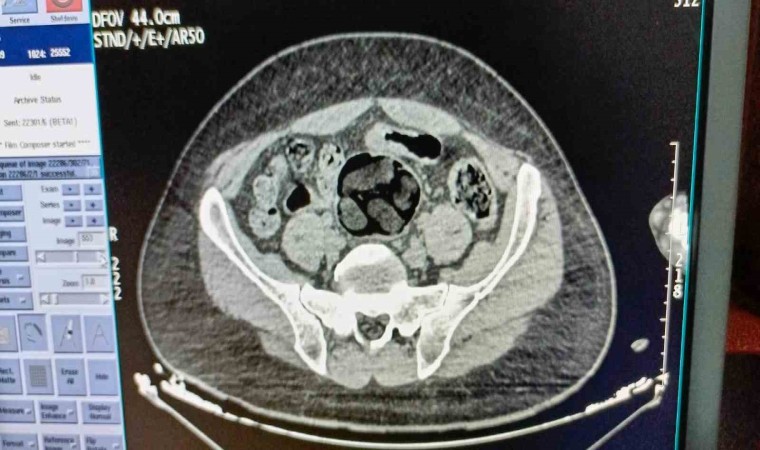

Kırşehir İl Emniyet Müdürlüğü Narkotik Suçlarla Mücadele Şube Müdürlüğü ekipleri tarafından yapılan çalışmalarda yabancı uyruklu Y.S. ve H.S.’nin doğu illerinden ülkeye kaçak yollarla girdikleri ve batı illerine uyuşturucu madde kuryeliği yaptıkları tespit edildi. Takibe alınan uyuşturucu kuryelerinin seyahat ettiği yolcu otobüsü Kırşehir’de durduruldu. Gözaltına alınan ve hastaneye götürülen şahısların midelerinde kapsül bulunduğu tespit edildi. Şahısların midelerinde zulaladığı 126 kapsül halinde 1 kilo 300 gram ve 44 kapsül halinde 550 gram uyuşturucu madde ele geçirildi.